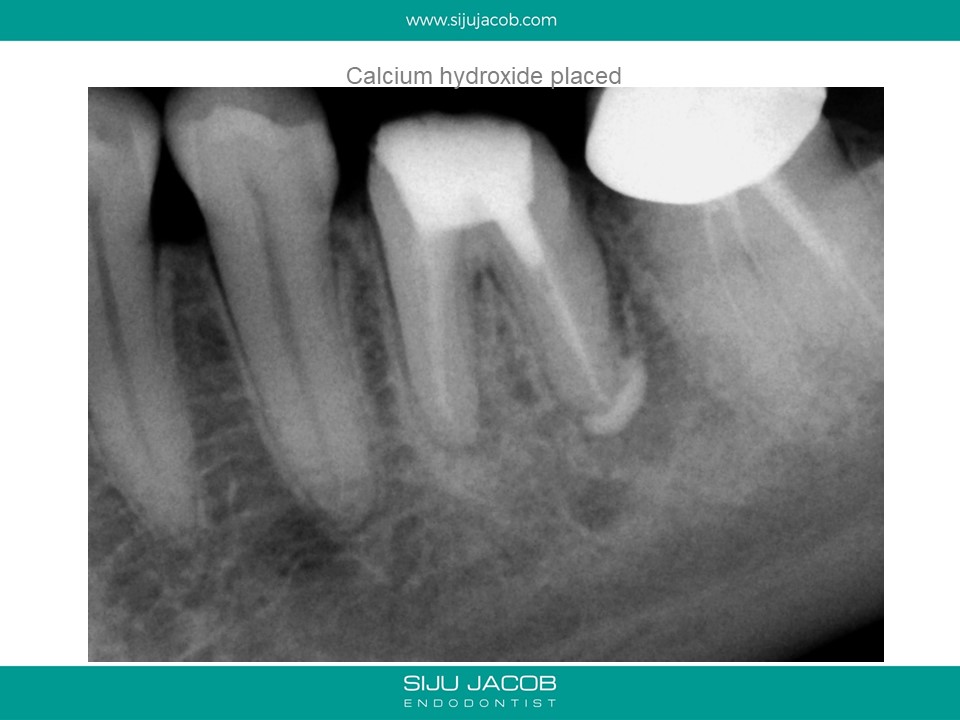

Written by Siju JacobApril 13, 2020 Molar Re-treat with large lesion This patient came with an acute abscess. Disassembly and re-treat with long term Caoh. One year recall shows healing. Share this: Share on X (Opens in new window) X Share on Facebook (Opens in new window) Facebook Like Loading... Related Leave a comment Cancel reply Δ